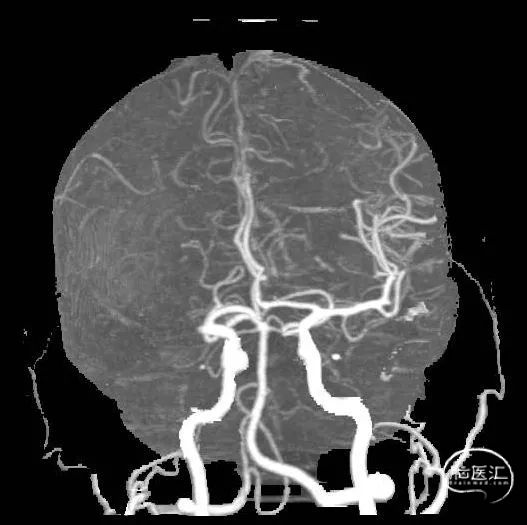

CTP+CTA显示右侧大脑中动脉M1闭塞,右侧大脑半球存在大面积缺血半暗带。

介入治疗指征:发病2小时,NIHSS评分12分,ASPECT9分,CTA示右侧大脑中动脉M1段闭塞,CTP示右侧大脑半球低灌注,Mismatch139.1ml。

造影显示右侧大脑中动脉M1闭塞。

右侧大脑中动脉取栓1次完全再通。